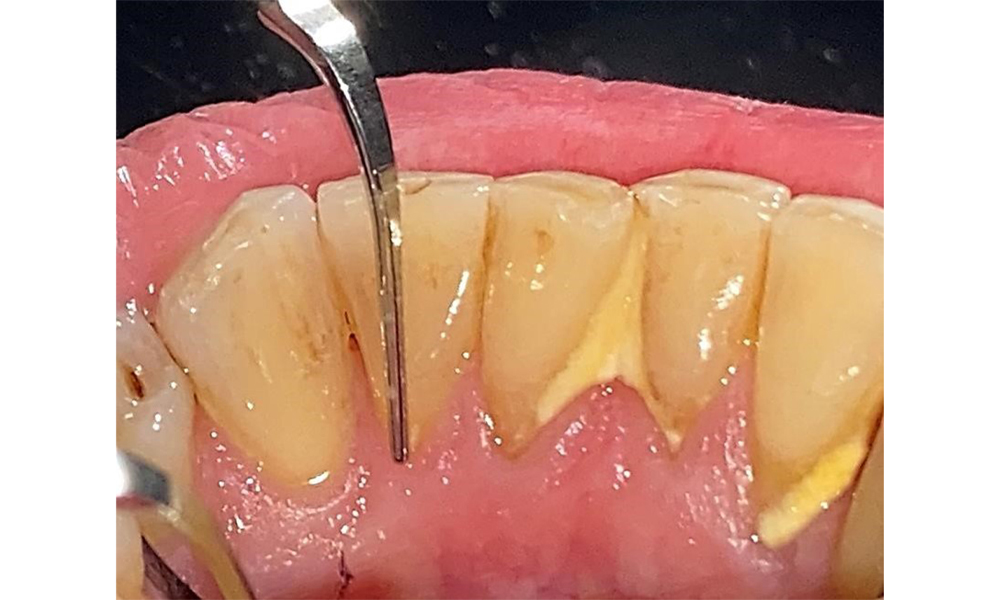

The patient uses interdental brushes and an electric toothbrush. This demonstrates good compliance and good intraoral hygiene behaviour and understanding at home. Regular motivation and re-instruction are indispensable due to the risk of progression, particularly with regard to the cleaning of interdental areas, since increased probing depths were detected in these areas. Localized calculus and soft plaque was present in the lingual anterior mandibular region, and these must be shown to the patient. The interdental brush size may need to be checked and adjusted. A soft brush attachment is recommended based on the presence of exposed root surfaces to prevent wedge-shaped defects. Toothpaste with a low abrasive value should be used.

There are no limitations regarding the choice of instrumentation methods. Regular supragingival and subgingival instrumentation is essential to prevent disease progression due to the pre-existing periodontitis and high risk of recurrence. There are no limitations placed on the selection of instruments for mechanical biofilm removal from a general medical perspective, and removal should be performed as needed. Hard and mineralized plaque, such as calculus and concretions, should be removed using manual instruments or sonic/ultrasonic scalers (Fig. 9) (8, 9).